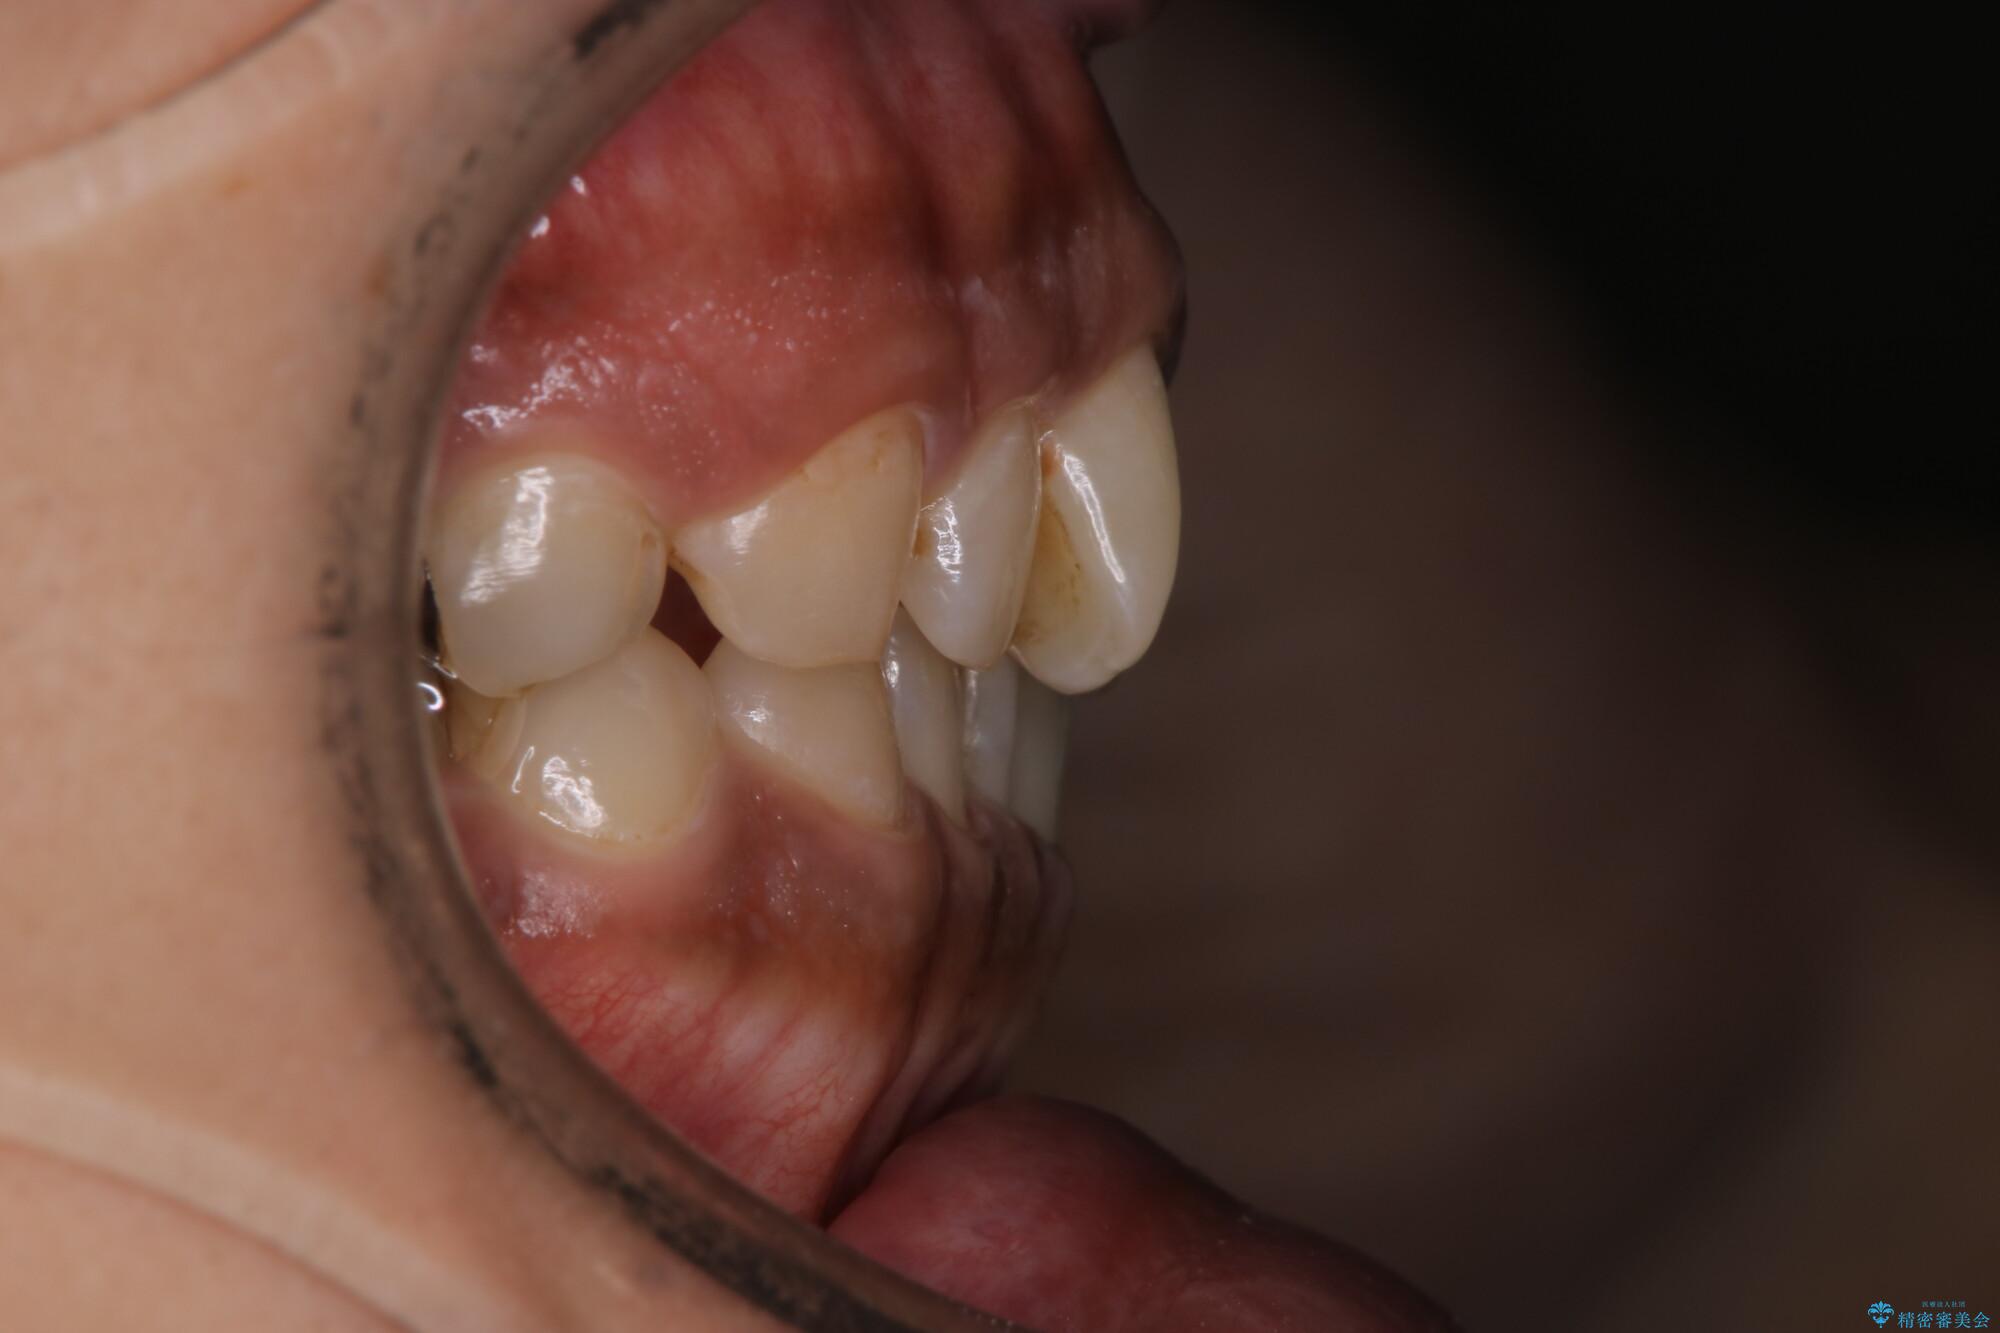

【モニター】インビザライン 前歯の捻れを治したい

- 30代男性

- 矯正装置

- インビザライン

- 治療期間

- 1年6ヶ月

- 治療計画

- 上下の前歯のがたつきを主訴に来院されました。インビザラインで治療可能と判断致しましたので、IPR(歯と歯の間を削る処置)と歯列弓拡大をして

がたつきをとる治療計画を立てました。

マウスピースをしっかり使用していただいたことで、主訴である前歯のがたつきも改善され

リファイメントも1回のみで治療を終了することが出来ました。